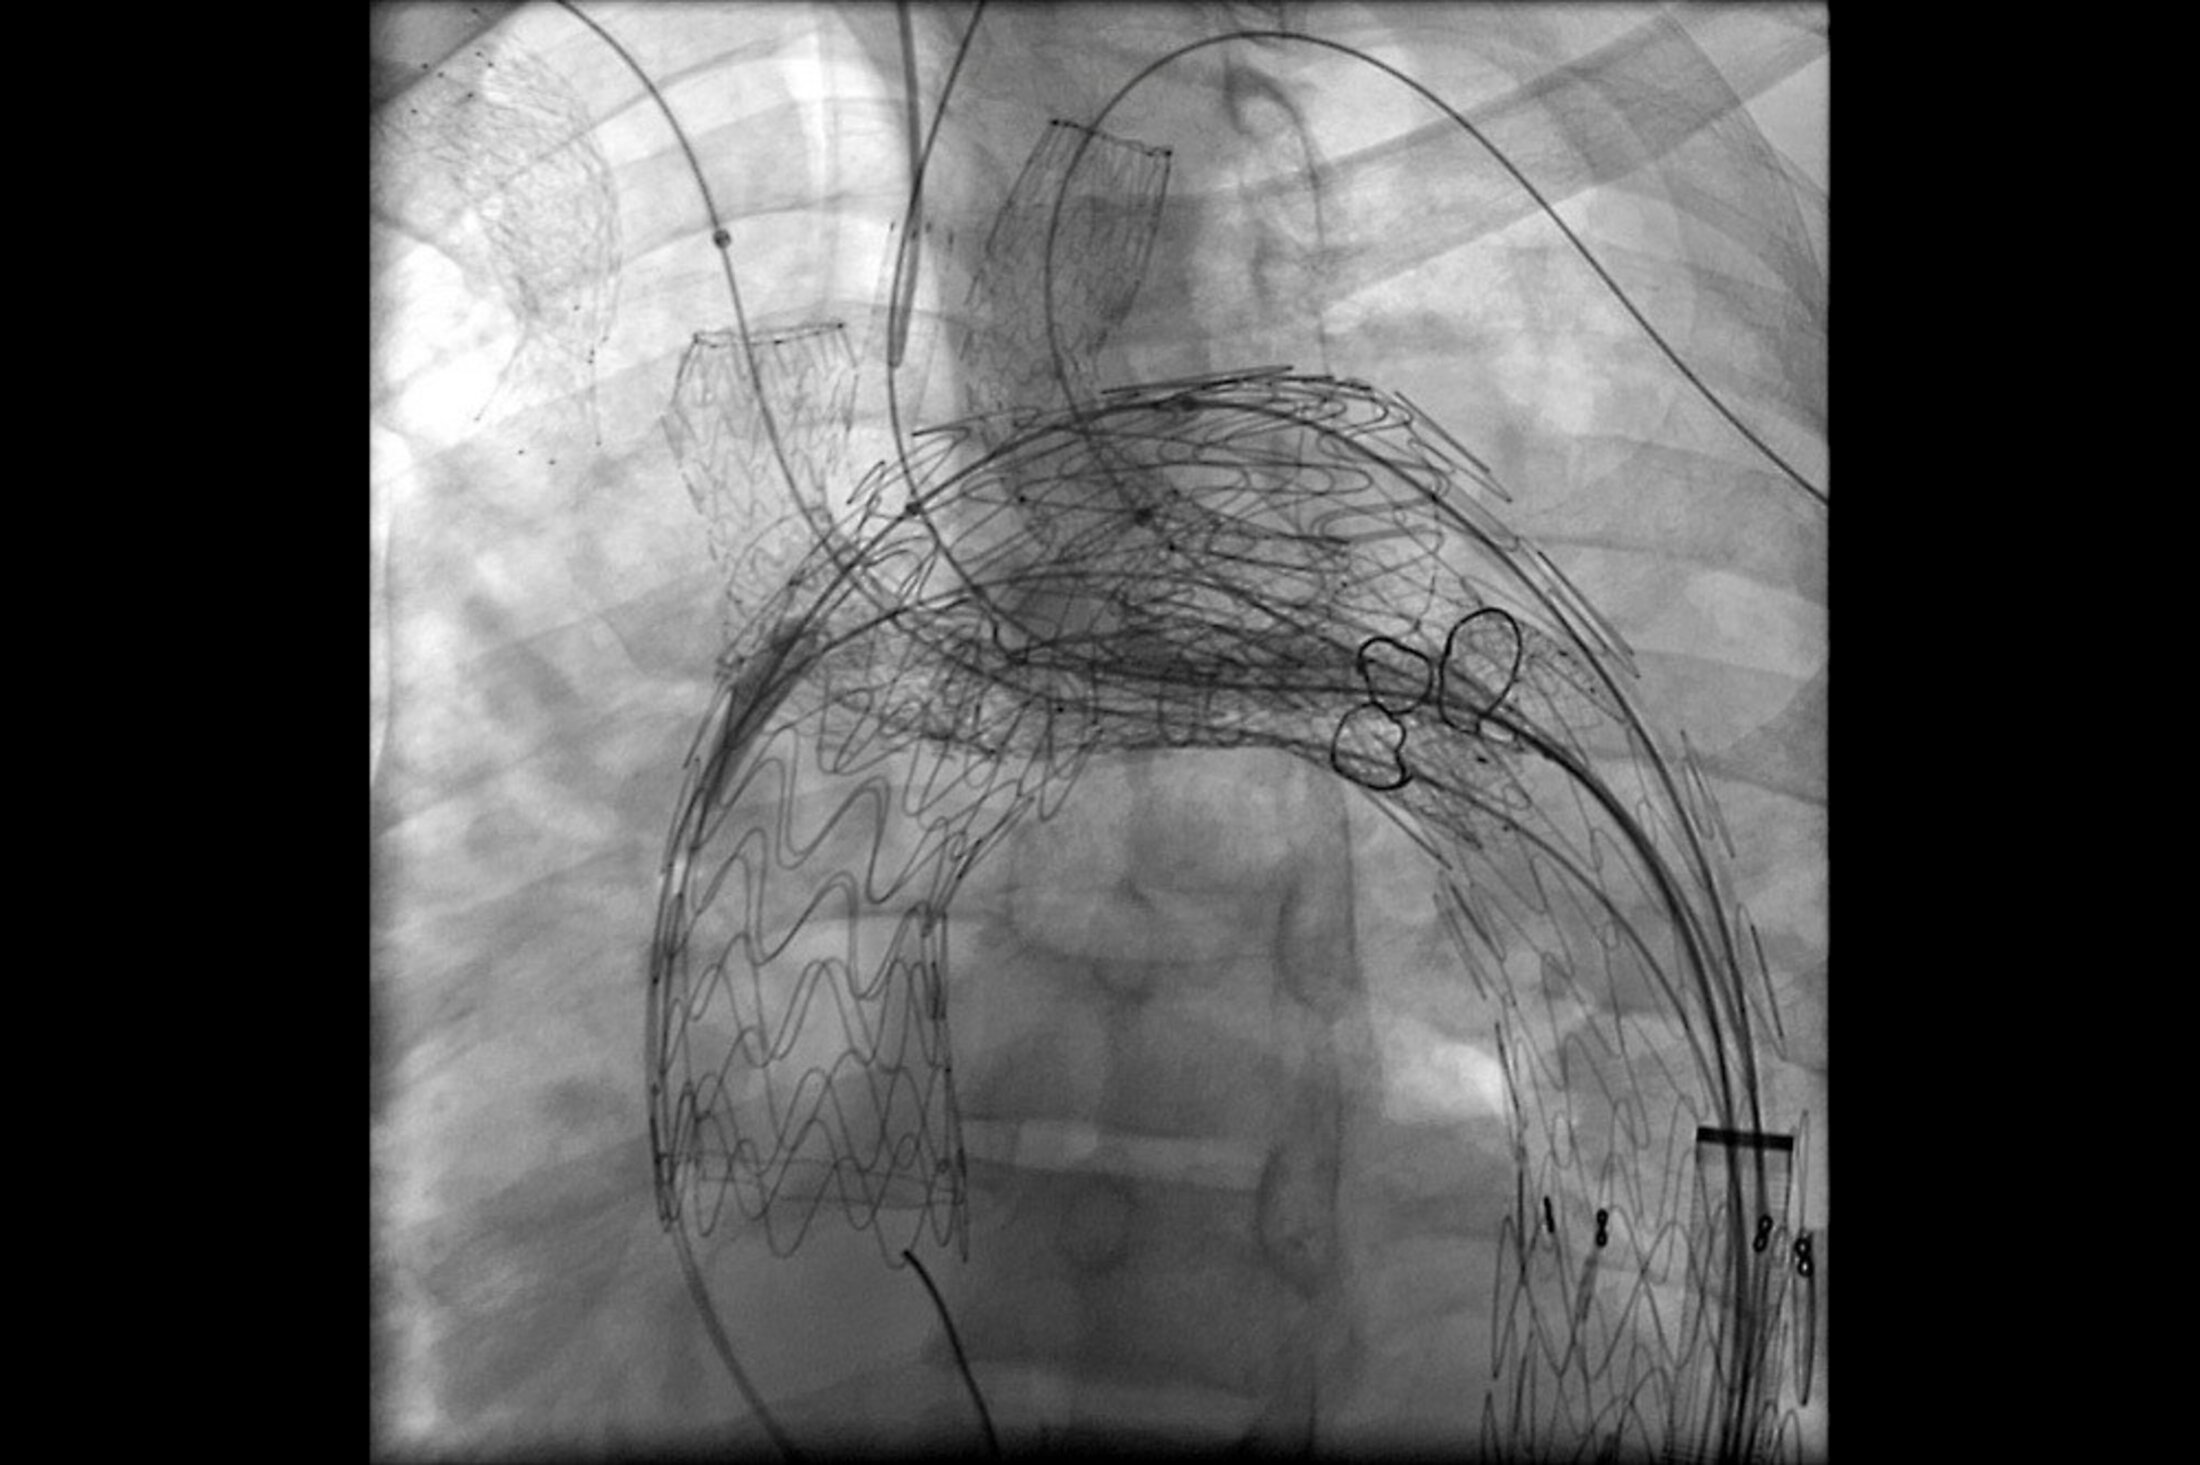

The new device allows doctors to treat aortic arch disease and proximal descending thoracic disease without surgery. Image provided

The disease involves the aorta, the largest artery in the body. Sometimes, part of its wall weakens due to a medical condition, genetics or trauma. Then, blood pressure can cause a bulge, or aneurysm, in that part of the wall. If the aneurysm gets too big, it can burst or tear the arterial wall. That’s what Wooster’s invention is designed to prevent. It uses what they call a graft, which is a tube, to shore up the weak part of the aorta. The design of the new system is what sets it apart.

“Essentially, our standard devices that existed for this are a straight sort of a tube. It's a cylinder made of plastic and metal that goes inside, and it's sort of like a spring that opens up inside of the body and holds itself against the aortic wall,” Wooster said.

“The next step to that is what we call fenestrated devices. They're things that have a single hole cut out in the side. And you line that hole up with the branches that go to the aortic arch.

“And then our design is sort of a modification of that, where we actually put it distal to the branches so it's not actually covering anything.” Distal means far from the branches of the the aorta.

“And it has three arms coming out of it. And then we eventually connect those arms up to the brain and up to your arms. So that it seals things off without ever having to obstruct the blood flow to those vessels.”